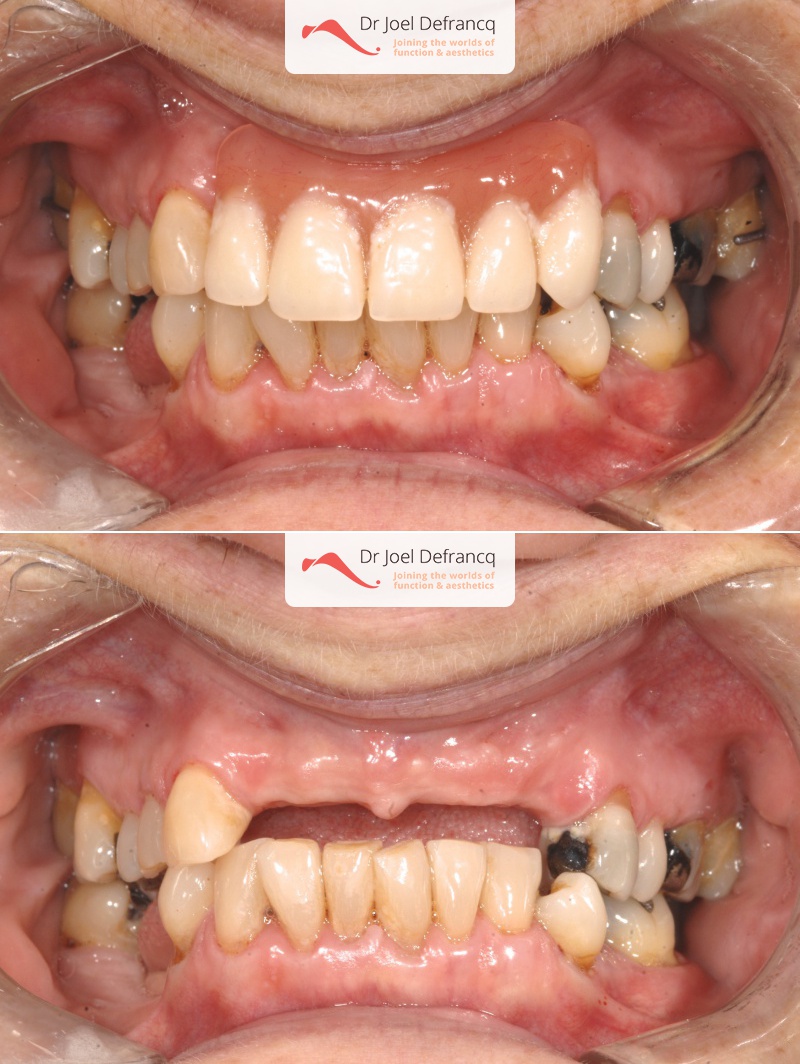

Axelle: new teeth in a week - implants.

Behandeling tandheelkundige implantaten

- Vaste tanden op implantaten (bovenkaak)